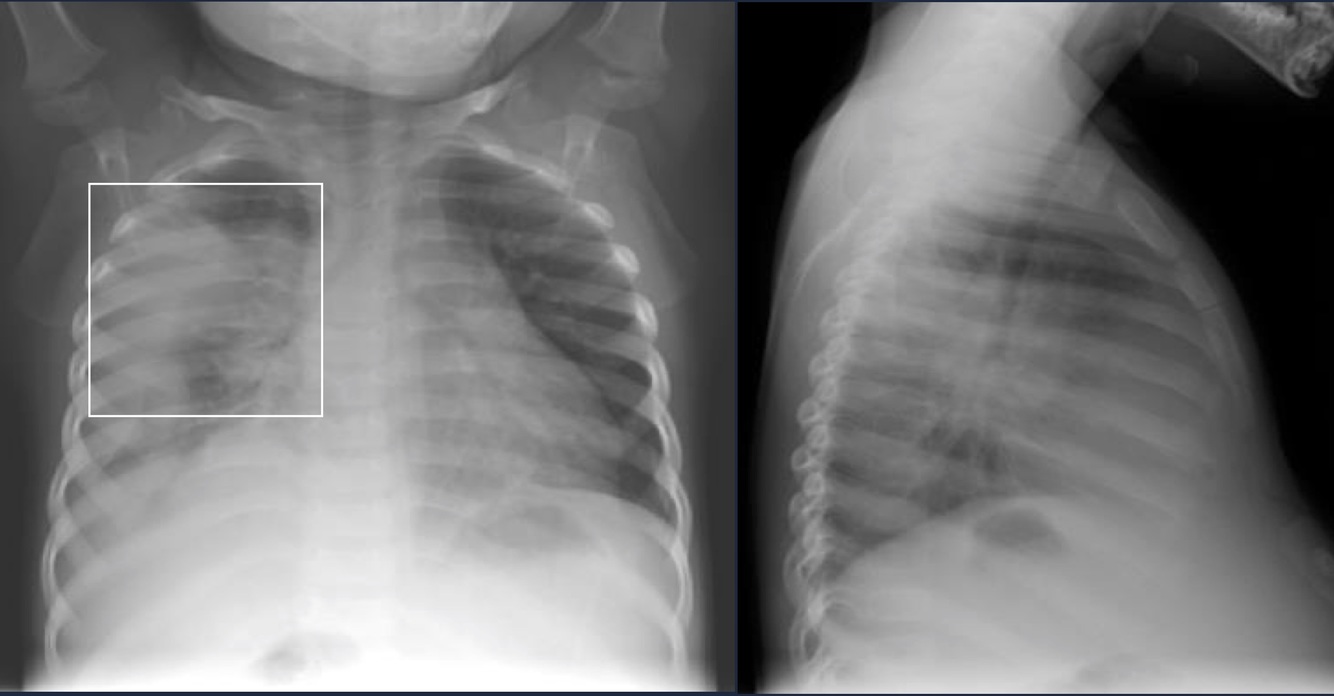

Atelectasis

Definition

Collapse of alveoli.

Causes

Lobar Atelectasis

Radiological sign ⇒ volume loss